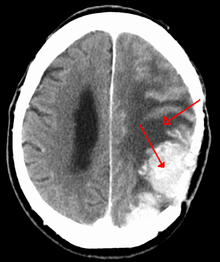

| A contrast-enhanced CT scan of the brain, demonstrating the appearance of a meningioma | |

Meningiomas are visualized readily with contrast CT, MRI with gadolinium,[14] and arteriography, all attributed to the fact that meningiomas are extra-axial and vascularized. CSF protein usually is elevated if lumbar puncture is attempted.